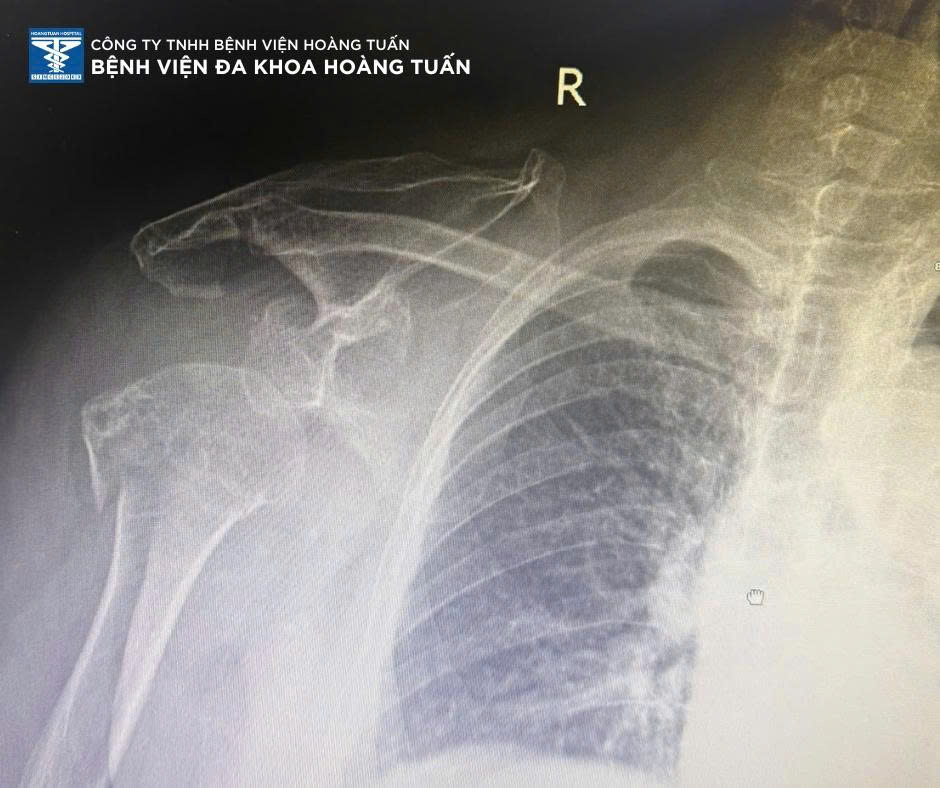

Bệnh viện Đa khoa Hoàng Tuấn vừa tiếp nhận bệnh nhân nữ 68 tuổi, nhập viện trong tình trạng đau nhiều và hạn chế vận động vai phải sau khi té ngã đập vai xuống nền gạch.

Qua thăm khám và chụp X-quang kiểm tra, BSCKI. Vũ Quốc Dũng – Khoa Ngoại CTCH Bệnh viện Đa khoa Hoàng Tuấn xác định bệnh nhân có tình trạng gãy đầu trên xương cánh tay phải kèm trật khớp vai phải, một tổn thương phức tạp, thường gặp ở người lớn tuổi do xương loãng, dễ gãy khi chấn thương.